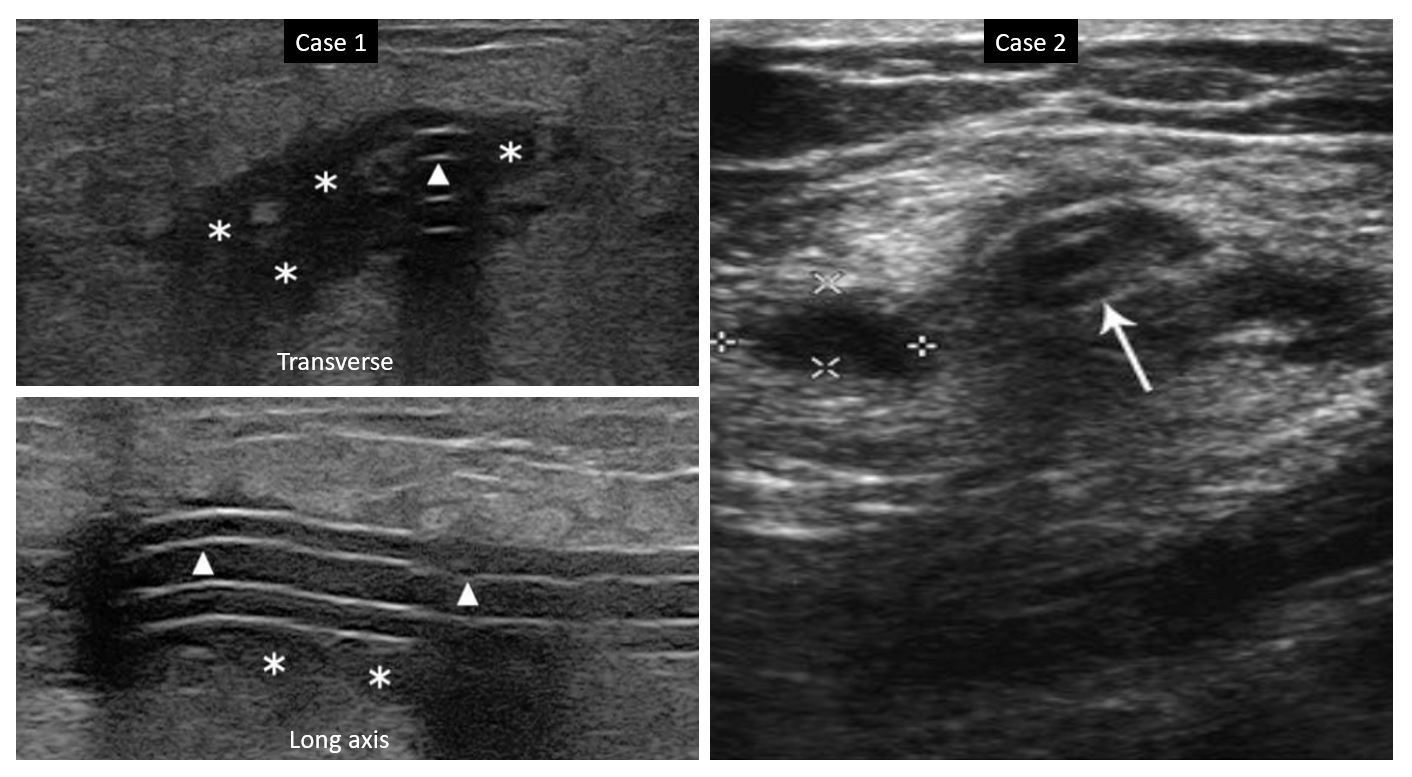

Bedside Ultrasonography of the Peritoneal Dialysis Catheter Renal Catheter Sepsis Dialysis (1) intravenous antibiotics alone, (2) prompt catheter removal with delayed placement of a new. This guideline applies to the management of central vascular catheters (cvc) once an infection is suspected, in patients of all ages. Catheter use in chronic hemodialysis patients has been recognized as distinct from other patient populations who require central venous access,. Arteriovenous fistula (avf) use is. Catheter Sepsis Dialysis.